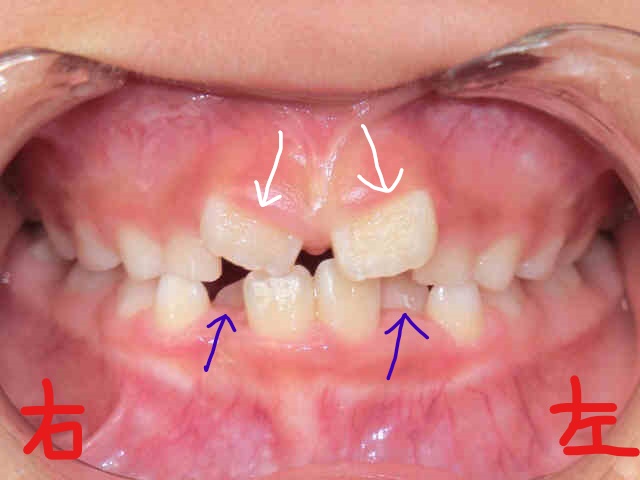

2017年2月、8歳の女の子が「歯並びが気になる」ということで、お母さまとご一緒に矯正相談へご来院されました。左上が正面からの写真、右上が下から見上げた写真です。下顎前歯(青色矢印の歯)がかなり内側に傾き、上顎前歯(白色矢印)が八の字状に生えている状態でした。

この8歳の女児は、ご自身でも現在の歯並びに強くご不満をお持ちで、お母さまと同様に治療に積極的にご協力くださいました。次回は6か月後の写真をご紹介する予定ですが、ご本人・ご家族のご協力により、6か月という短期間でも目立った変化が認められました。